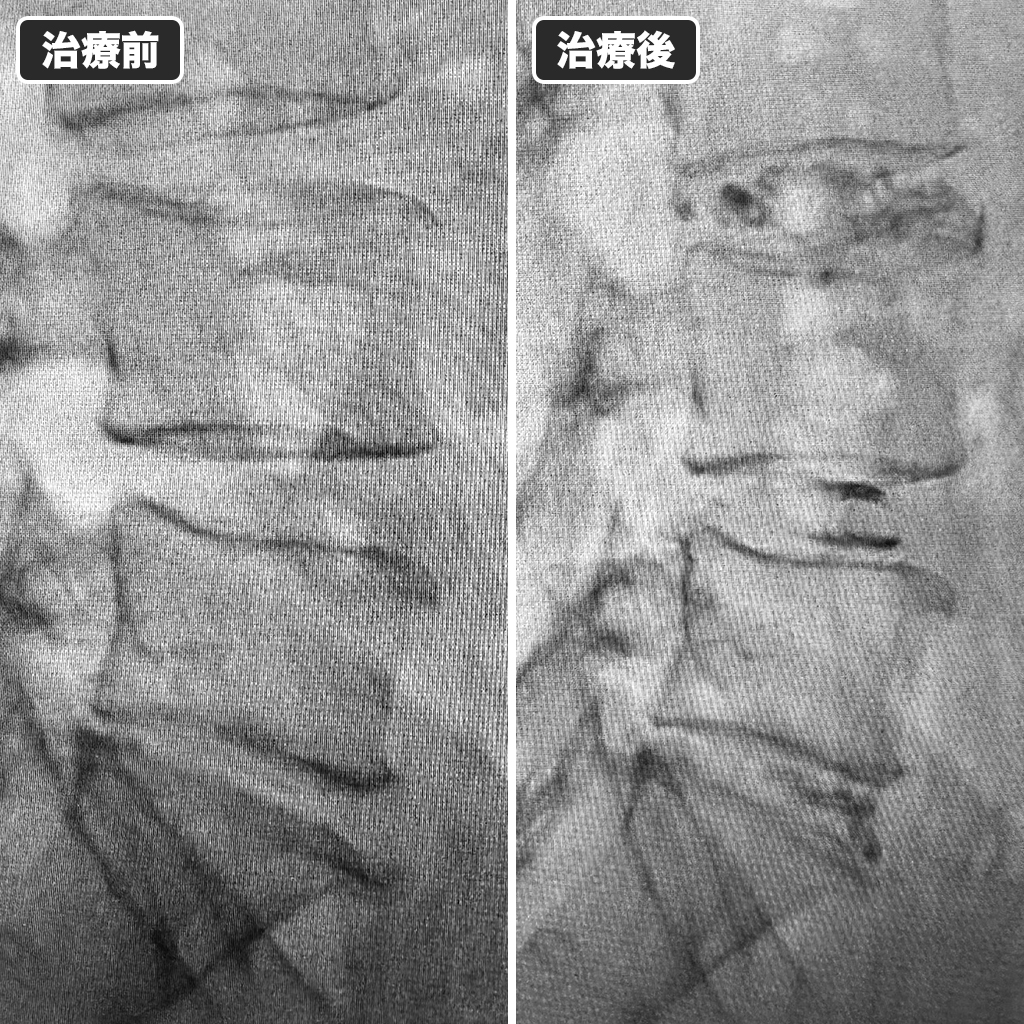

治療前後のレントゲン写真

治療前後のレントゲン写真です。左側が治療前、右側が治療後になります。